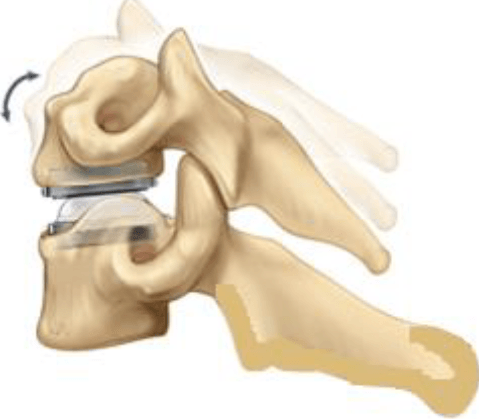

After fusion you may notice some range of motion loss, but this varies according to neck mobility before surgery and the number of levels fused. If only one level is fused, you may have similar or even better range of motion than before surgery. If more than two levels are fused, you may notice limits in turning your head and looking up and down. Motion-preserving artificial disc replacements have emerged as an alternative to fusion. Similar to knee replacement, the artificial disc is inserted into the damaged joint space and preserves motion, whereas fusion eliminates motion. Outcomes for artificial disc compared to ACDF are similar, but long-term results of motion preservation and adjacent level disease are not yet proven. Talk with your surgeon about whether ACDF or artificial disc replacement is most appropriate for you.

Figure 7. Artificial disc replacement preserves motion of the spine segment. Alternative option: artificial disc replacement (Fig. 7). Instead of a bone graft or fusion cage, an artificial disc device is inserted into the empty disc space. In select patients, it may be beneficial to preserve motion. Talk to your doctor – not all insurance companies will pay for this new technology and out-of-pocket expenses may be incurred.